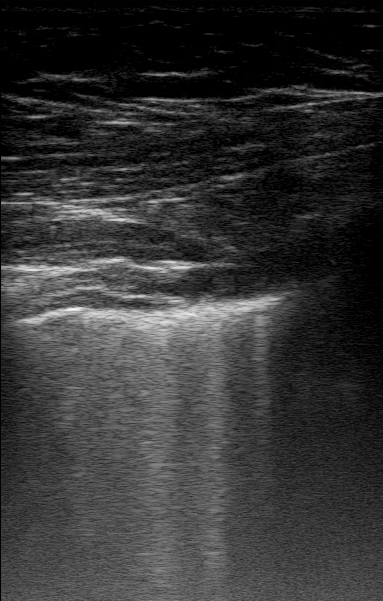

We compiled a lung ultrasound dataset of linear probe videos consisting of 189 patients (718 videos) with multiple (minimum 2 per patient) ultrasound B-scans of left and right lung regions at depths ranging from 4cm to 6cm under different scan settings, obtained using a Sonosite X-Porte ultrasound machine. (Fig. 3 in supplementary material highlights the various dataset distribution.)